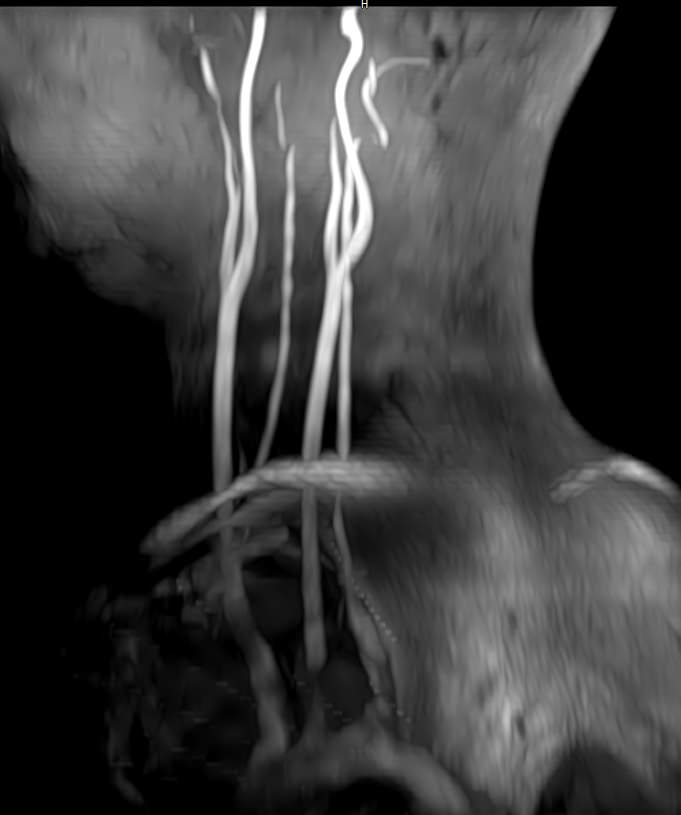

В клинике «Доступная медицина» проводится комплексное исследование: МР-ангиография шеи и головного мозга на новейшем высокопольном томографе экспертного уровня TOSHIBA VANTAGE TITAN 1,5 Тесла, который создает изображения сосудистой системы превосходного качества, что позволяет проводить точную диагностику и назначать пациенту своевременное лечение. МР-ангиография проводится в стандартном режиме без использования контраста.

- Суть исследования МРТ сосудов шеи и головного мозга

Суть исследования МРТ сосудов шеи и головного мозга

Для обнаружения заболеваний шеи, зачастую доктора назначают особые технологии проверки, например Доплер или рентген-анализ. Но бывают ситуации, связанные с вероятностью наличия в теле пациента аномальных процессов, происходящих в мягких тканях, тогда врачи выписывают направление на прохождение МРТ сосудов шеи. Подобное обследование показывает даже самые мелкие и незначительные изменения.